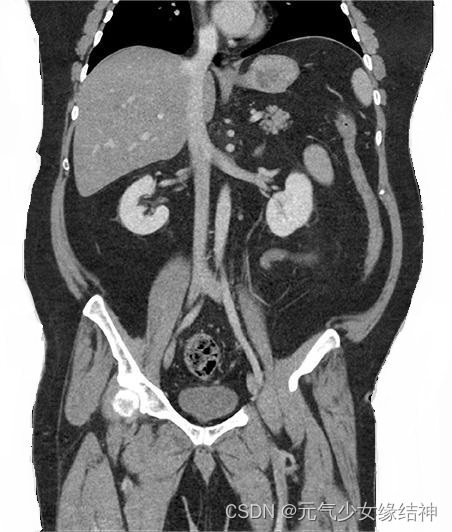

对以下CT图片进行去噪:

左边是原图,右边是去噪后的结果。去噪的同时规避细节模糊的弊端,肌肉和骨头细节保存完整:

对以下CT图片进行去噪:

左边是原图,右边是去噪后的结果。去噪的同时规避细节模糊的弊端,肌肉和骨头细节保存完整: